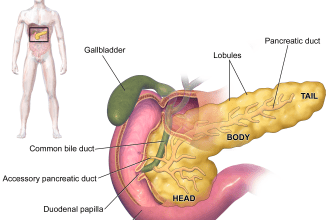

Have you ever heard of the reversal of normal organ